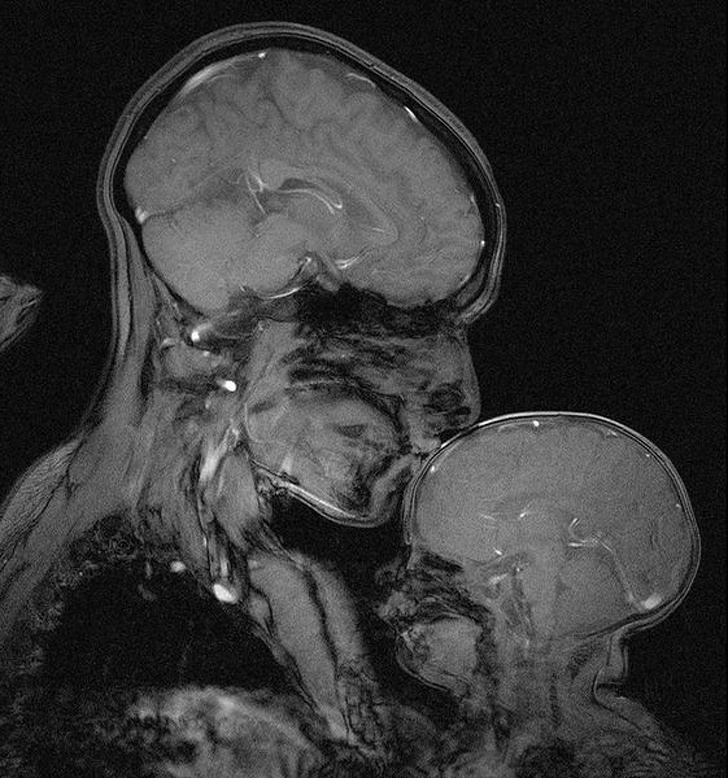

6. Жінка з немовлям в апараті МРТ